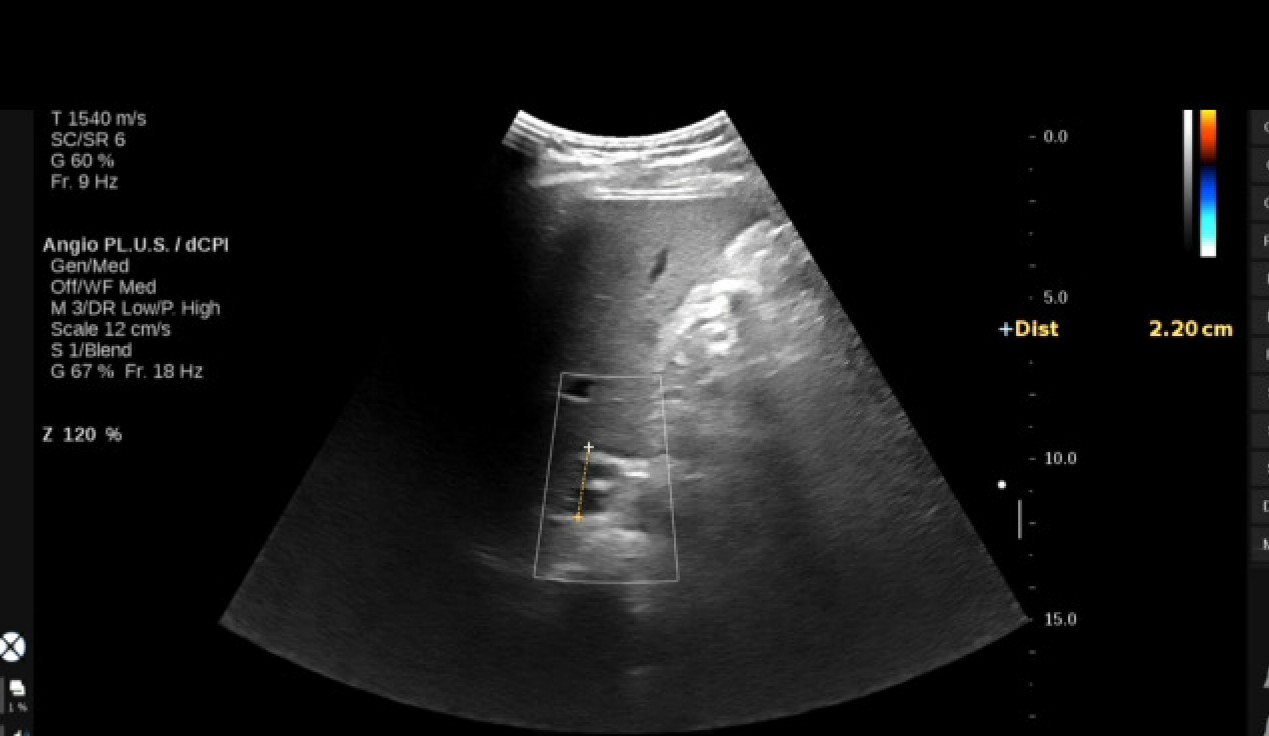

VIETNAMESE MEDIC ULTRASOUND CASE 686 GASTRODUODENAL ARTERIAL ANEURYSM Medic Medical Diagnostic Center Vietnam Công ty tnhh y tế hoà hảo. trung tâm y khoa medic. dịch vụ khám bệnh và kỹ thuật chẩn đoán. Phạm vi được công nhận. Hãy tải app “”medic hòa hảo”” đăng ký sử dụng, để được nhanh. Vilas med 041 hiệu lực công nhận/ period of accreditation: medic lab (medic medical center) cơ quan chủ. Medic Medical Diagnostic Center Vietnam.

From www.ultrasoundmedicvn.com